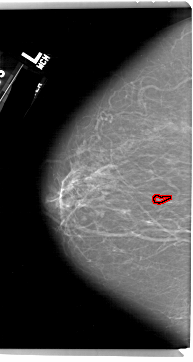

A_1192_1.LEFT_MLO

LEFT_MLO LINES 6856 PIXELS_PER_LINE 3856 BITS_PER_PIXEL 12 RESOLUTION 43.5 OVERLAY

FILE: A_1192_1.LEFT_MLO.OVERLAY

TOTAL_ABNORMALITIES 1

ABNORMALITY 1

LESION_TYPE CALCIFICATION TYPE FINE_LINEAR_BRANCHING DISTRIBUTION LINEAR

ASSESSMENT 4

SUBTLETY 2

PATHOLOGY MALIGNANT

TOTAL_OUTLINES 1

BOUNDARY